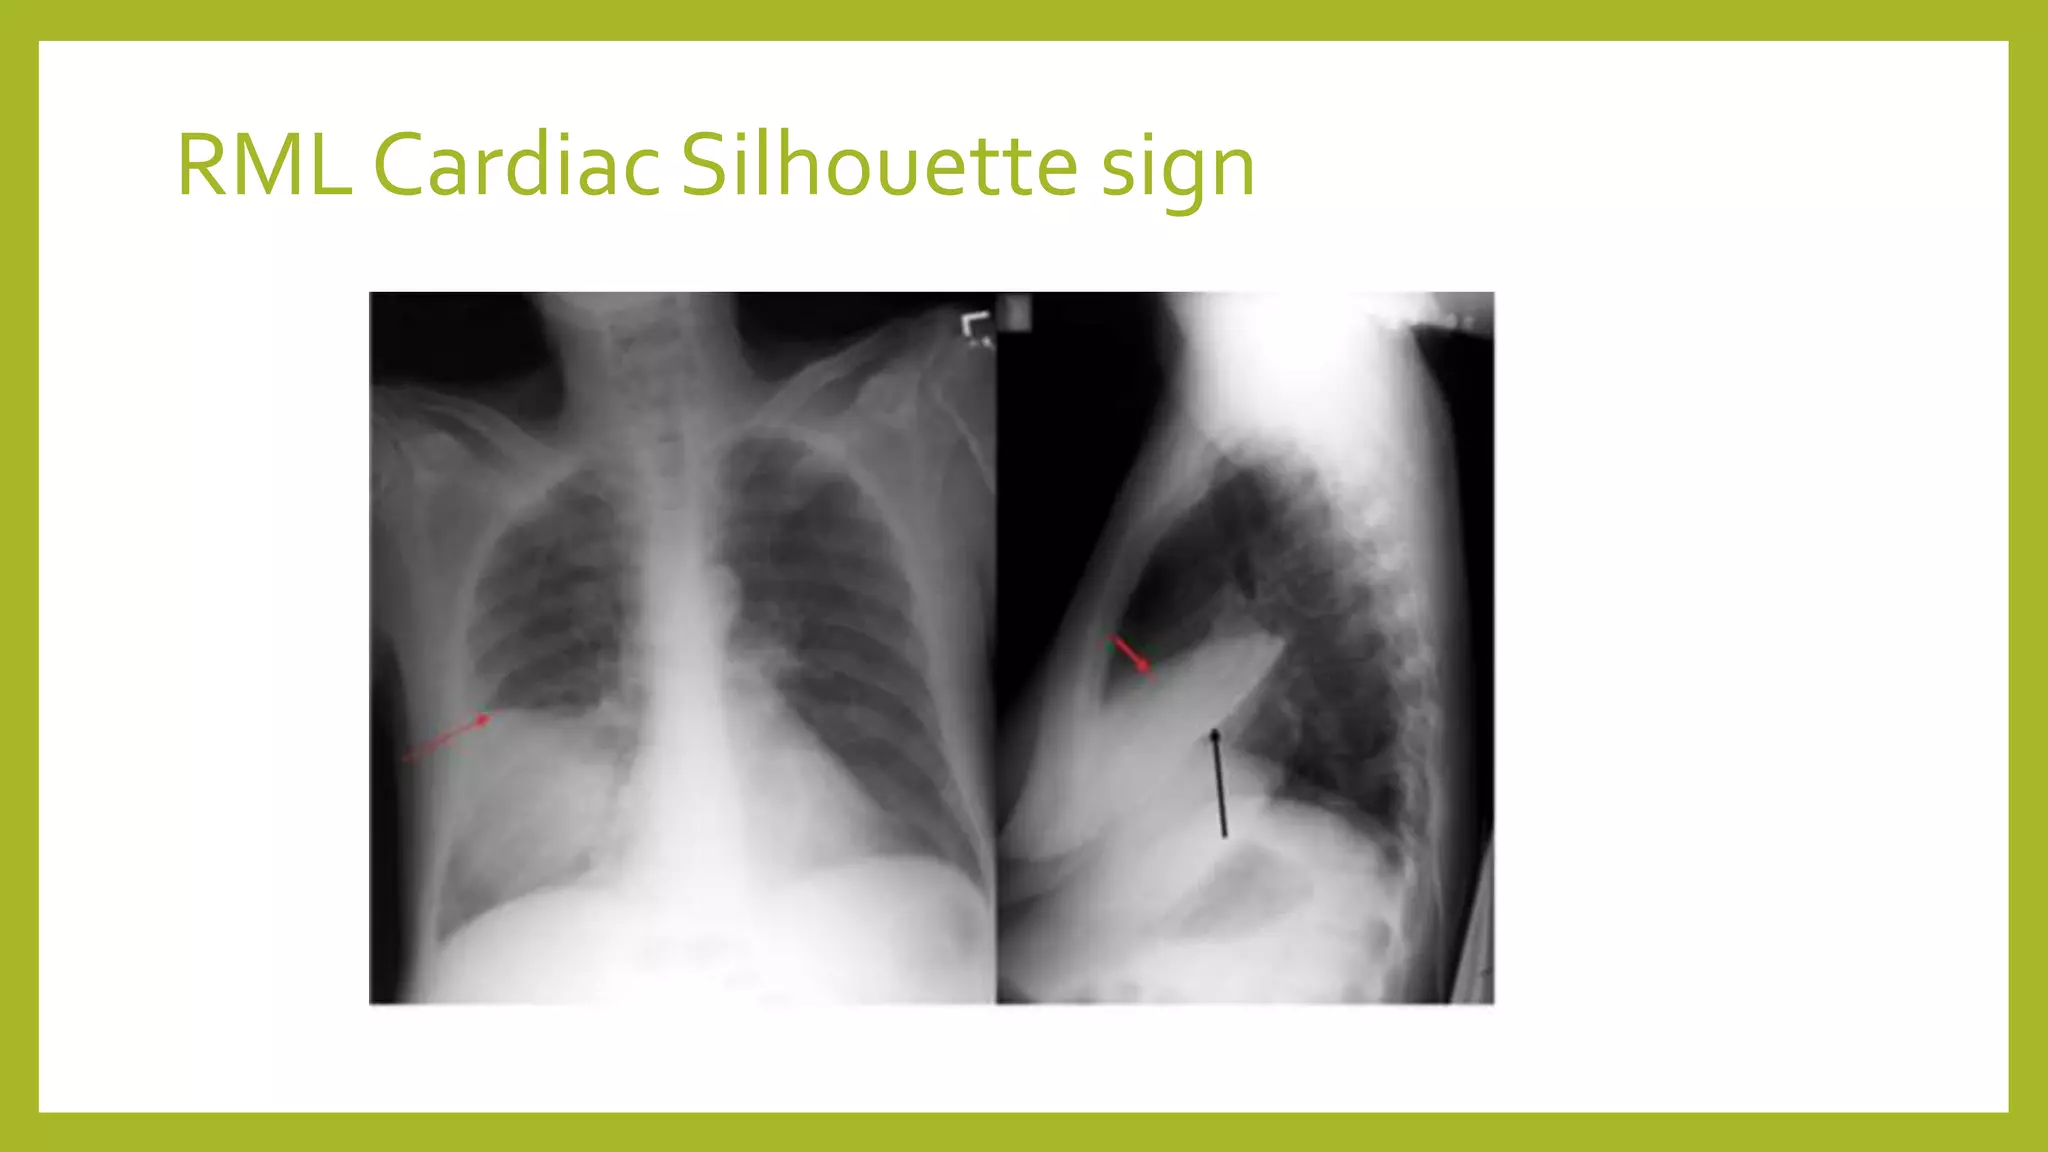

The document provides guidance on approaching and interpreting chest x-rays (CXR). It outlines steps to check the name, date and quality of the film, systematically scan the CXR looking for abnormalities, and determine if the lungs appear too white or black. Specific signs are described to help localize abnormalities, including the cardiac silhouette sign and pleural effusion signs. Examples are given of respiratory distress syndrome, tetralogy of fallot, transposition of great arteries, and total anomalous pulmonary venous return. The take home message is to summarize positive findings, compare to prior CXRs if available, and confirm findings with a radiologist.